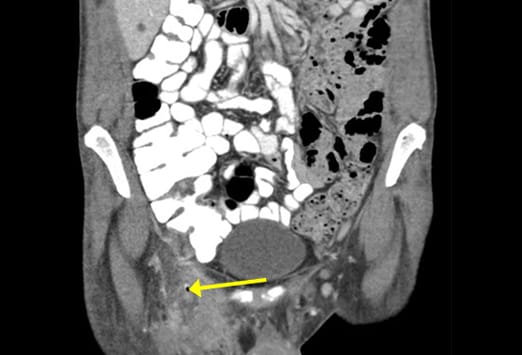

Ein Mann im mittleren Alter wird vorstellig mit Fieber und einem eiternden Leistenabszess. Diese koronaren CT-Aufnahmen zeigen eine im Femoralkanal eingeklemmte Appendix. Die Häufigkeit einer Hernierung der Appendix in eine Schenkelhernie liegt bei <1%; insgesamt kommt dieses Ereignis bei weniger als 0,13% aller Appendizitiden vor. [4] Schenkelhernien sind häufig angeborene Defekte; sie treten häufiger beim weiblichen Geschlecht auf. Aufgrund der Enge und Festigkeit des Femoralkanals ist die Rate an inkarzerierten Schenkelhernien (14-56%) signifikant höher als die der Leistenhernien (6-10%); aus diesem Grund sollte eine frühzeitige operative Therapie erfolgen.